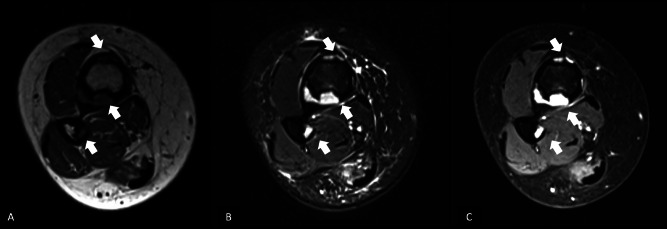

教学点:骨纤维结构不良(OFD)是一种罕见的良性纤维骨性病变,主要影响儿童和青少年的胫骨皮质;腓骨同时受累是罕见的,可能类似于更具侵袭性的肿瘤,如adamantinoma。

Teaching point: Osteofibrous dysplasia (OFD) is a rare benign fibro‑osseous lesion primarily affecting the tibial cortex in children and adolescents; simultaneous involvement of the fibula is exceptional and may mimic more aggressive tumors such as adamantinoma.